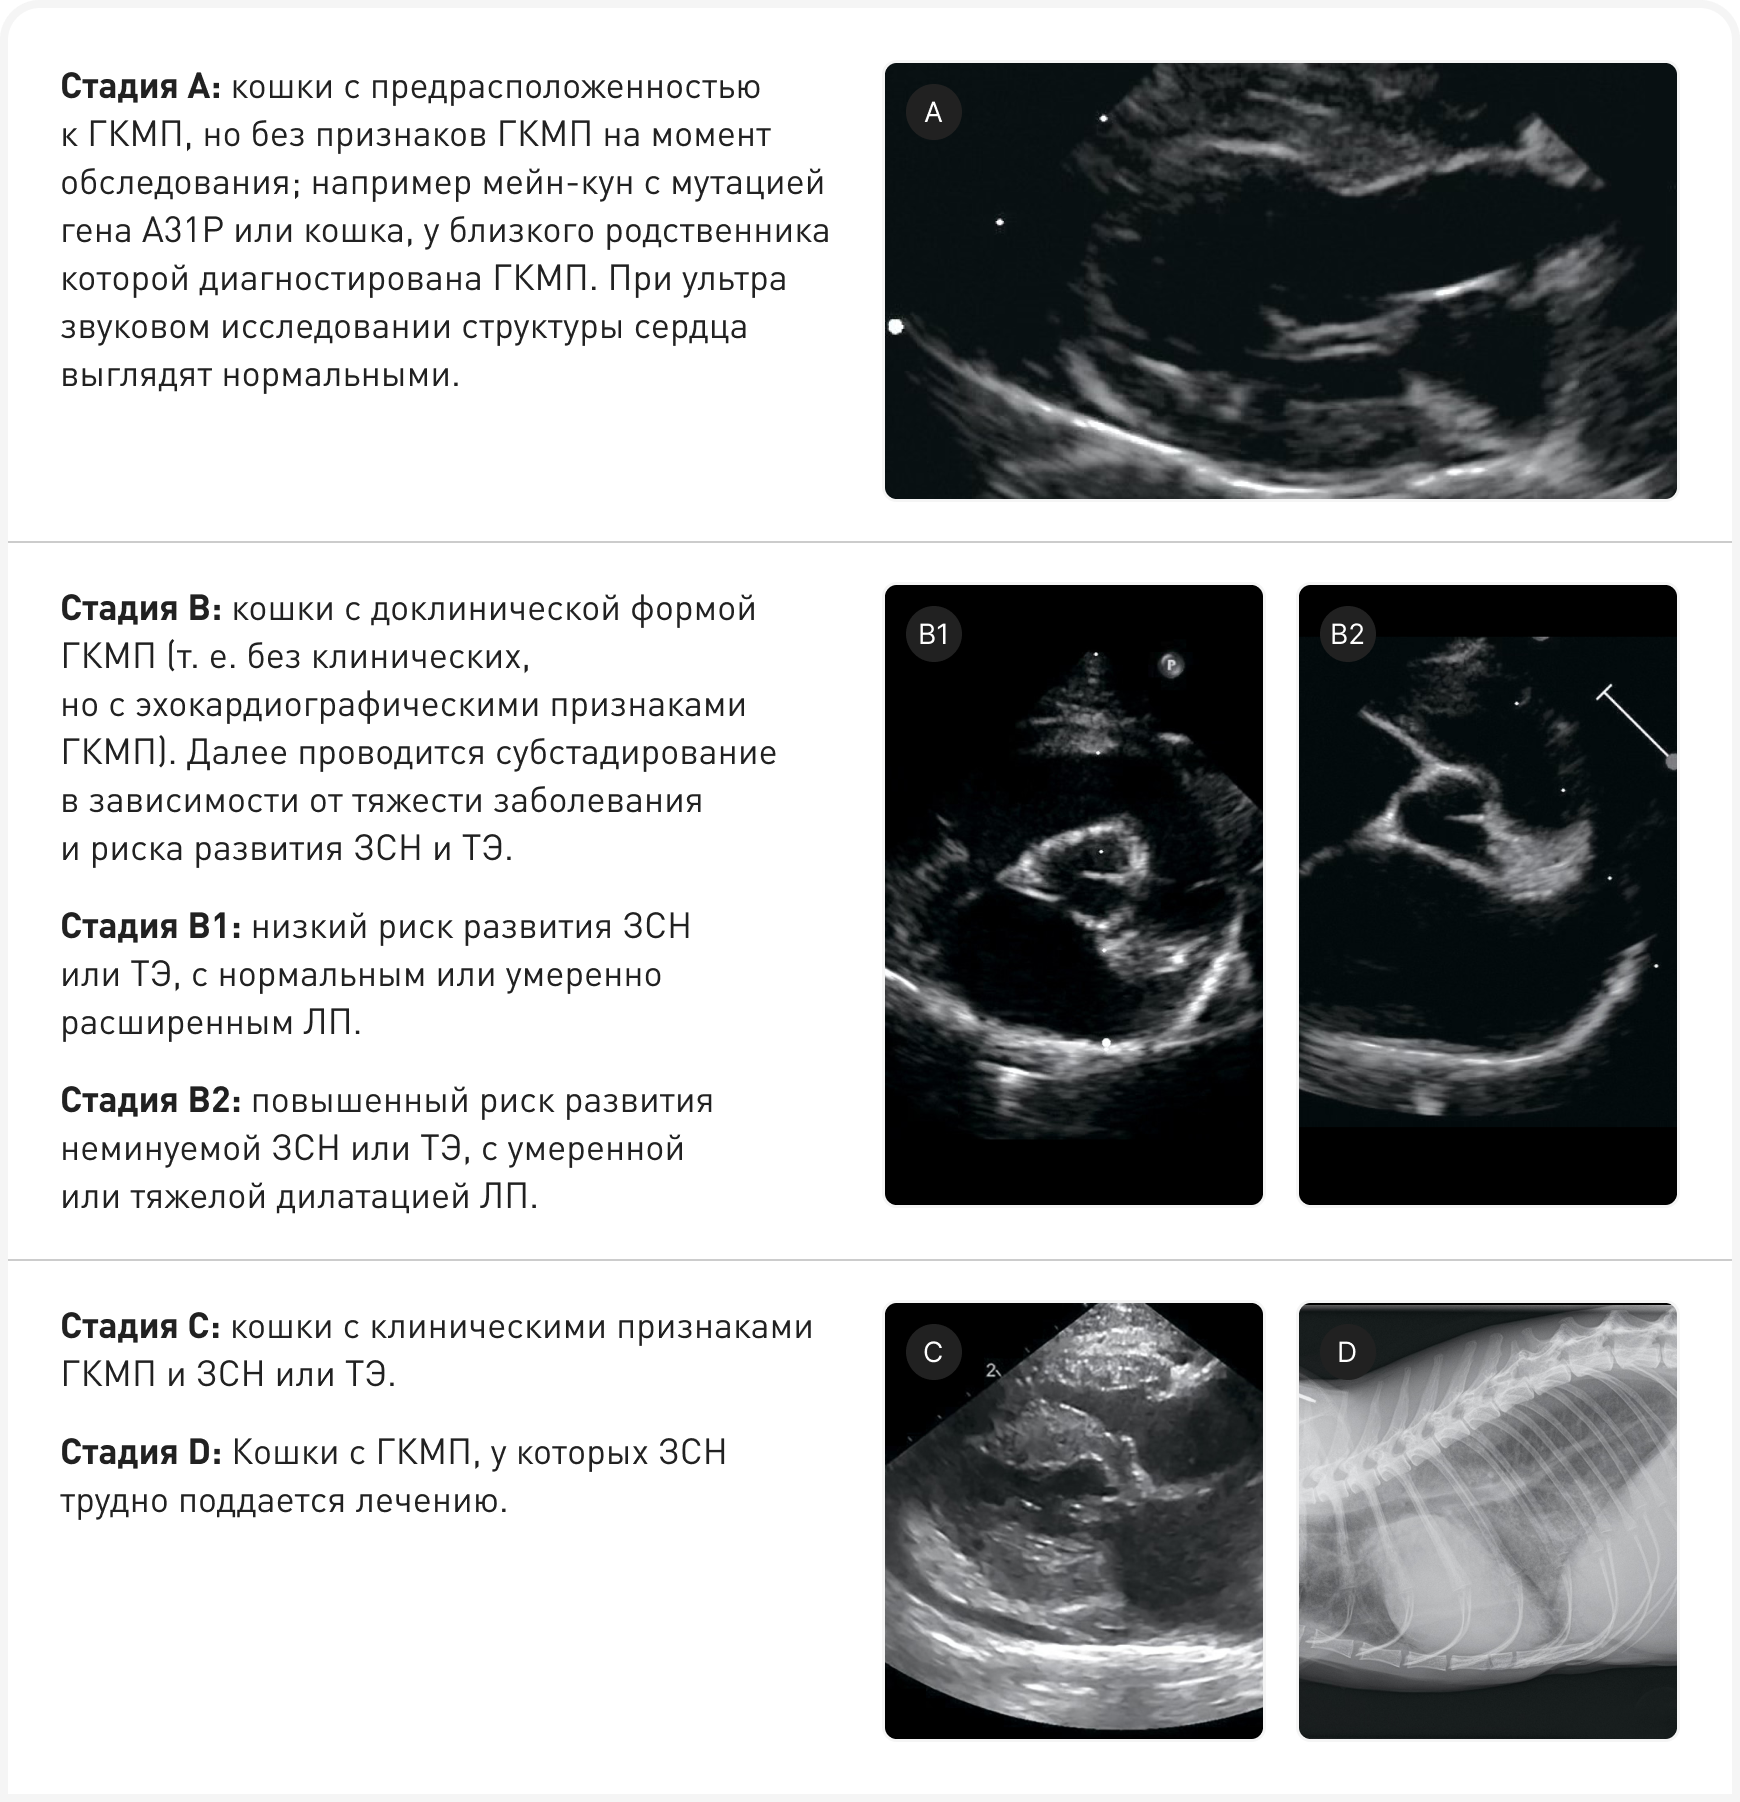

Оценка стадии и прогноз ГКМП

В последних рекомендациях ACVIM по диагностике и лечению ГКМП (14) изложена система оценки стадий, аналогичная используемой при миксоматозном поражении митрального клапана у собак (Блок 1). Эта система может помочь определить, показано ли лечение, а также дать владельцам некоторое представление о том, что ждет животное в будущем, поскольку прогрессирование ГКМП, а значит и прогноз, очень изменчивы. У некоторых кошек болезнь прогрессирует, приводя к развитию ЗСН, ТЭ и сердечной смерти, в то время как у других может оставаться на доклинической стадии, и животные умирают от не связанных с заболеванием сердца причин (14, 15).

Причина такой гетерогенности неизвестна, и предсказать, какие кошки могут погибнуть от болезни, трудно, хотя в нескольких ретроспективных исследованиях был выявлен ряд прогностических факторов. Выживаемость кошек, которым диагноз был установлен в более молодом возрасте, обычно выше (2). Выживаемость кошек при ЗСН, вызванной стрессом или внутривенными инфузиями (IVFT), обычно выше, чем при ГКМП на стадии С, вызванной другими причинами. Наличие ритма галопа, аритмии, выраженного расширения ЛП, снижения систолической функции ЛП, спонтанного эхоконтрастирования, выраженной гипертрофии стенок сердца (>9 мм), систолической дисфункции и очагового истончения стенки ЛЖ ассоциируется с повышенным риском развития ЗСН и/или ТЭ (2, 15).